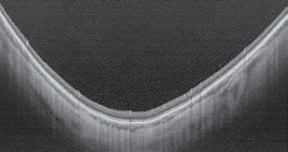

VISUMAX 800 Hands-on Demo

Book a hands-on demonstration of the ZEISS VISUMAX 800 in our dedicated ZEISS Corneal Refractive room and experience lenticule extraction with ZEISS SMILE pro option for faster cut speeds1 and easier tissue separation2